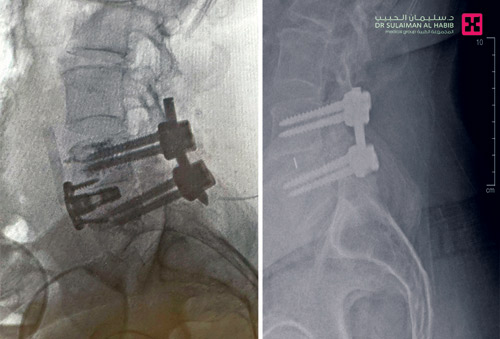

وقال د. محمد السفياني استشاري جراحة العمود الفقري للكبار والأطفال، رئيس الفريق الطبي المعالج، أن الفحوصات التي أجريت للمريض أظهرت وجود تزحزح للغضروف الصناعي للخلف مع تخلخل وعدم ثبات البراغي. وقد ناقش الفريق الحالة على ضوء معطيات التشخيص، والحالة الصحية العامة للمريض، خصوصاً أن محاولة إزالة الغضروف المتزحزح من الخلف عن طريق الظهر ستشكل خطورة عالية على الأعصاب بسبب الإلتصاقات الناتجة عن العملية السابقة.

وقد قرر الفريق الطبي إجراء عمليتين للمريض في وقت واحد؛ وتم في العملية الأولى الدخول عن طريق البطن من الأمام لإزالة الغضروف الاصطناعي المتزحزح وتركيب دعامة جديدة ALIF بمساعدة د. ناصر الوهيبي استشاري جراحة الأوعية الدموية للتأكد من سلامة الشرايين الرئيسية بالبطن. وبعد ذلك تم إجراء العملية الثانية من الظهر في نفس موقع العملية السابقة، وتم تبديل المسامير بمسامير إسمنتية. ومضت العمليتان بسلاسة وانتهت ولله الحمد بالنجاح التام، ونقل المريض إلى غرفة التنويم، حيث أمضى «5» أيام تحسنت حالته خلالها، واستعاد قدرته على المشي بعد نحو «36» ساعة من العملية، وغادر المستشفى بحالة صحية ونفسية ممتازة، وقد تخلص من معظم الأعراض التي عانى منها وتراجعت حدة المتبقي منها، وعاد لممارسة حياته بصورة طبيعية.